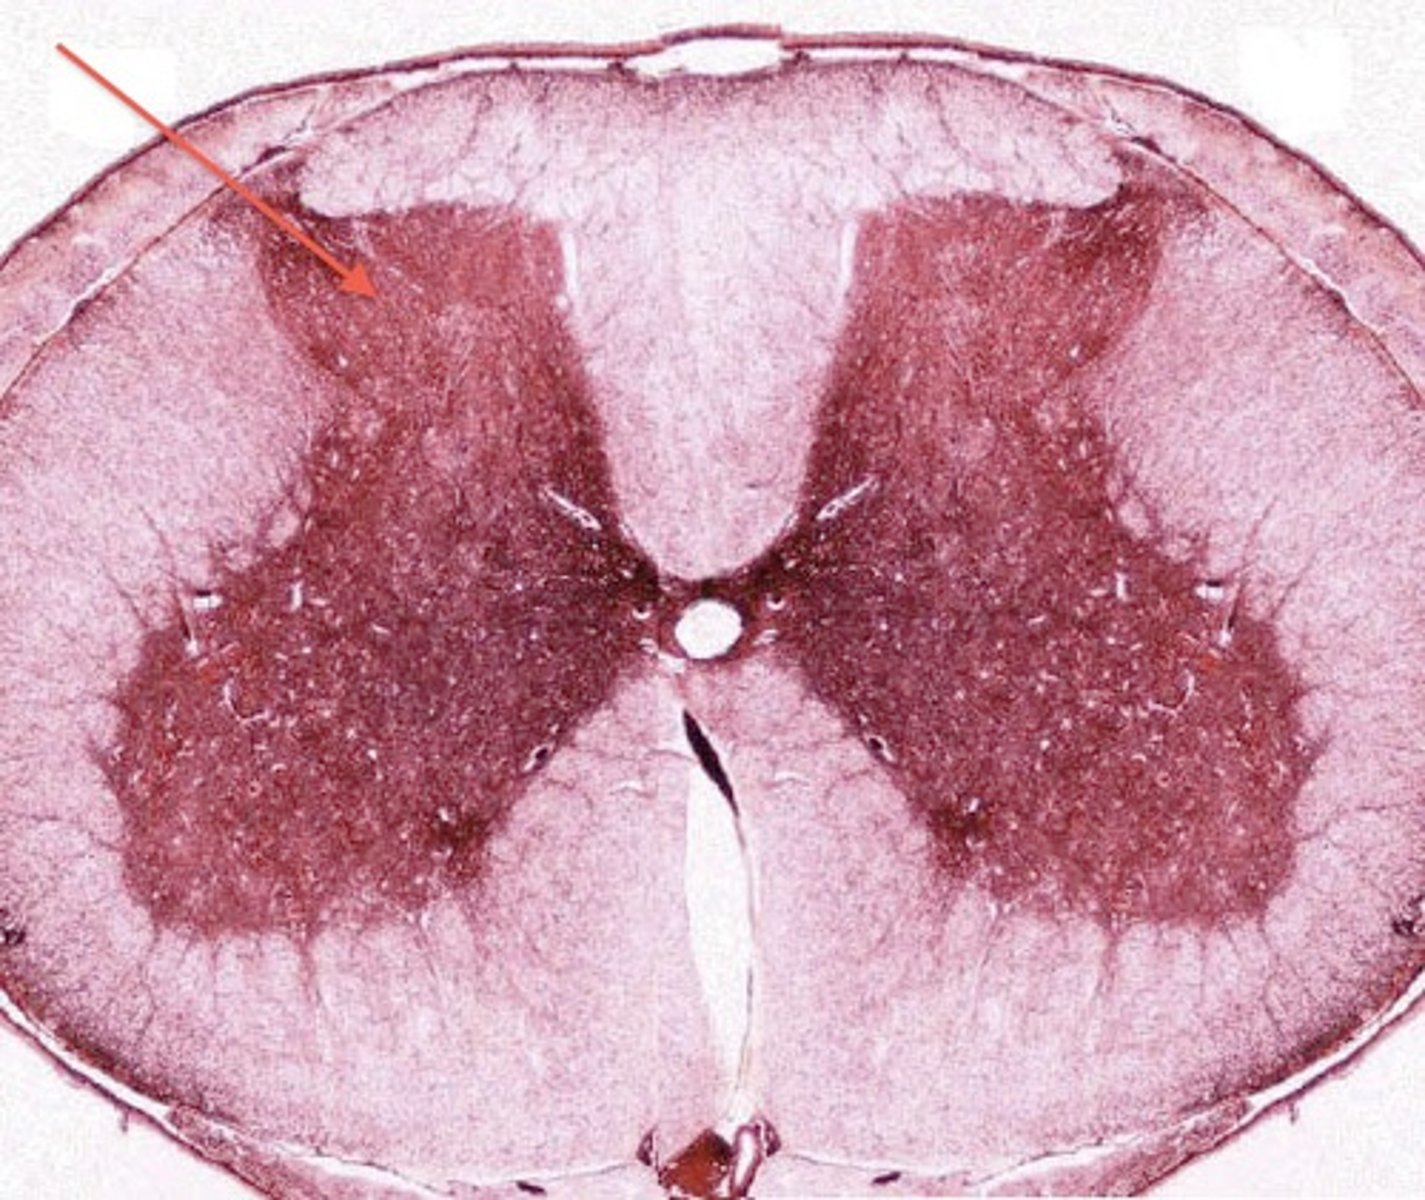

white matter

made up of myelinated axons found largerly in CNS. Cerebral cortex, outer surface of spinal chord

grey matter

made up of unmyelinated axons and cell bodies. Slower signal transmission. inner layer of spinal cord.

Ventral horn

multipolar motor nerve cell bodies

lateral horn

Dorsal horn

dorsal funiculus

ventral funiculus

lateral funiculus

central canal

filled with cerebral spinal fluid

gray commissure

cross bar of butterfly

posterior median sulcus

anterior median sulcus